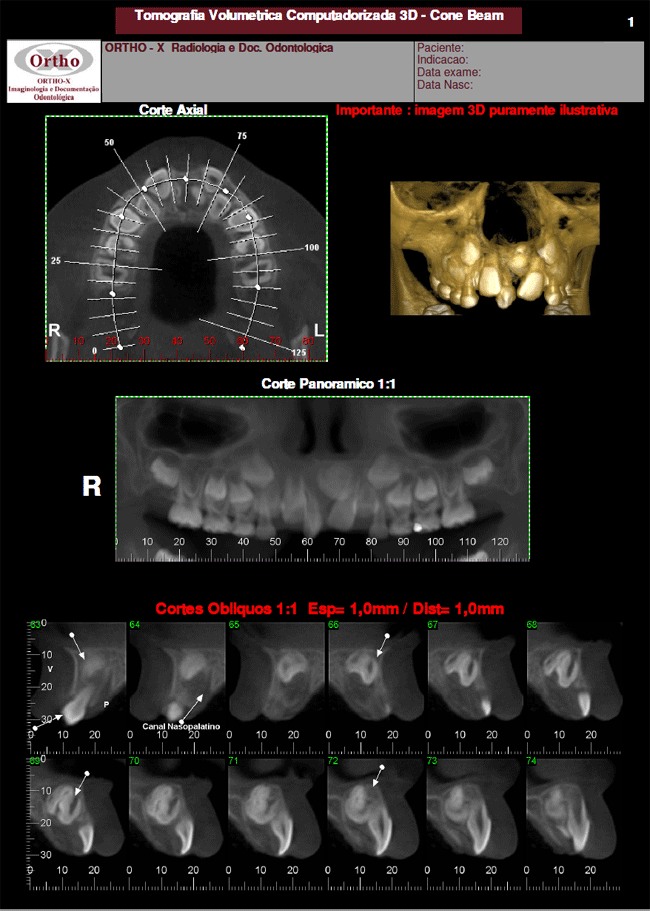

Exames > Tomografia Computadorizada 3D > Exemplo de Exames: Supranumérico

Exemplo de Exames: Supranumérico